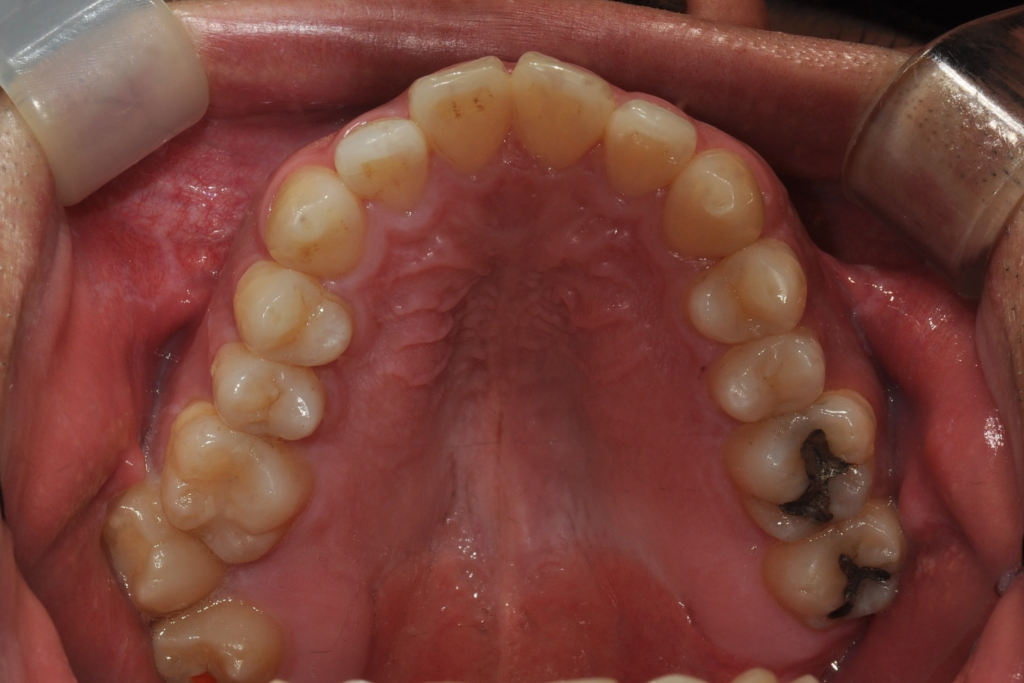

현재 저는 상악 7번 대구치 가위교합( 바깥쪽) 나와 있는 상황입니다. 7번,8번 모두 치아 상태는 괜찮다고 들었습니다.

저 또한 7번 사용을 하고 싶으나, 많이 돌출 되어 있어서 옮기다가 잇몸 등에 영향을 줄까 고민이 됩니다 ㅠ

• 2번 째 사진